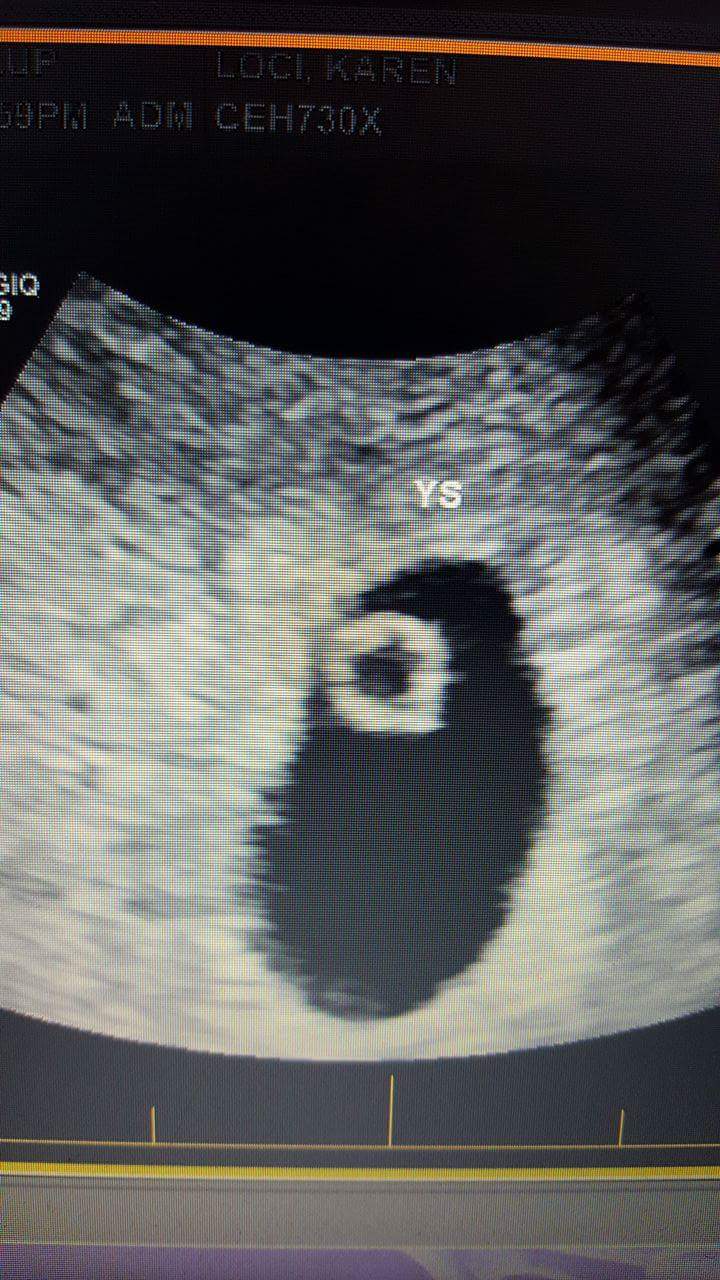

3rd,4th,5th and 6th are 12 week shots